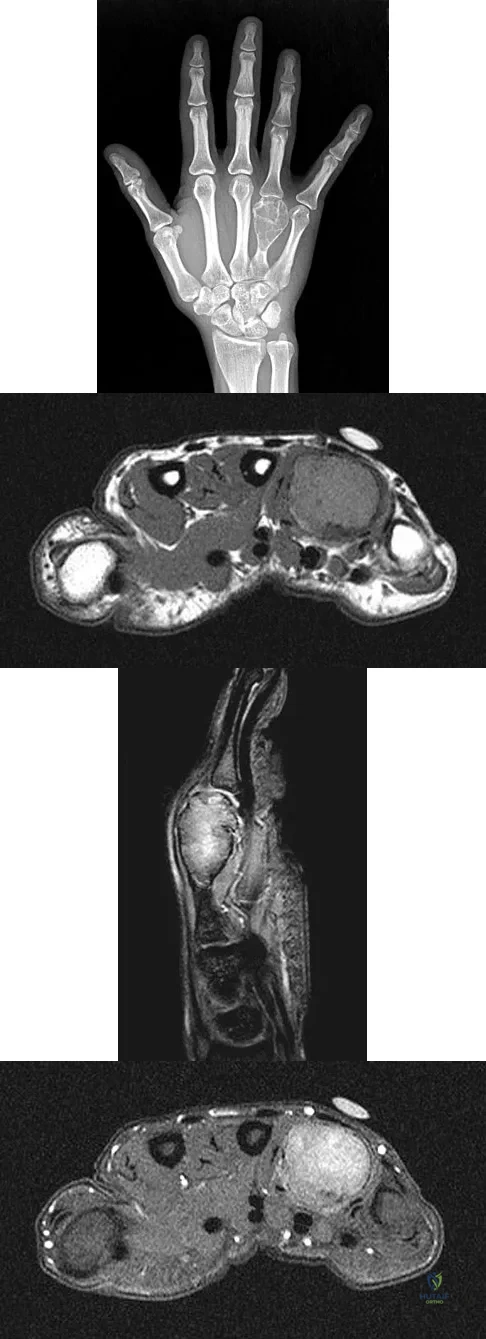

Question 76

A 26-year-old man has had hand pain and progressive swelling in the knuckle for the past several months. He denies any trauma to the hand. The ring finger metacarpophalangeal joint is tender, and there is loss of motion in the digit. Figure 32a shows the radiograph and Figures 32b through 32d show the T1-weighted, T2-weighted, and gadolinium MRI scans, respectively. What is the most likely diagnosis?

Explanation